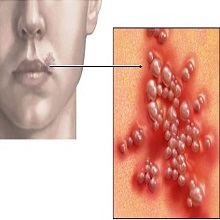

| Инфекција коже, захвата површни слој коже. У око 90% случајева обољења изазивач инфекције је СТАФИЛОКОК. Локални налаз се исполљава у виду црвенила након чега долази до стварања пустула и була које се пуне гнојним садржајем. |

„Herpes labialis" („herpes febrilis") – је веома честа грозница. Може се појавити на уснама, носу, устима и образу. Узрокује га херпес-вирус тип 1. Херпес вирус тип 2 обично узрокује инфекцију на полним органима. Оба вируса могу узроковати појаву плика на лицу и полним органима. |